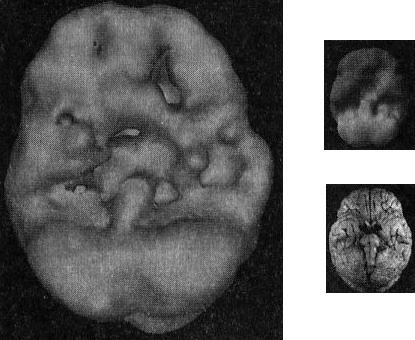

Среди многих моих пациентов мне особенно запомнился 26-летний Марк с синдромом Туретта (СТ) — расстройством, при котором возникают моторные и вокальные тики. Около 15 % людей с СТ страдают от копролалии, то есть компульсивного сквернословия. В нашу клинику Марк попал в середине прохождения курса реабилитации от наркотиков. Когда я в пятый раз спросил, была ли у него травма головы, он начал раздражаться: «Черт побери, нет!» Посмотрев на его скан (рис. 4.1), я проявил настойчивость и спросил, может, он занимался спортом.

Черепно-мозговая травма Марка (снимок поверхности)

Рис. 4.1 Вид снизу

Обратите внимание на низкую активность с левой стороны мозга Марка